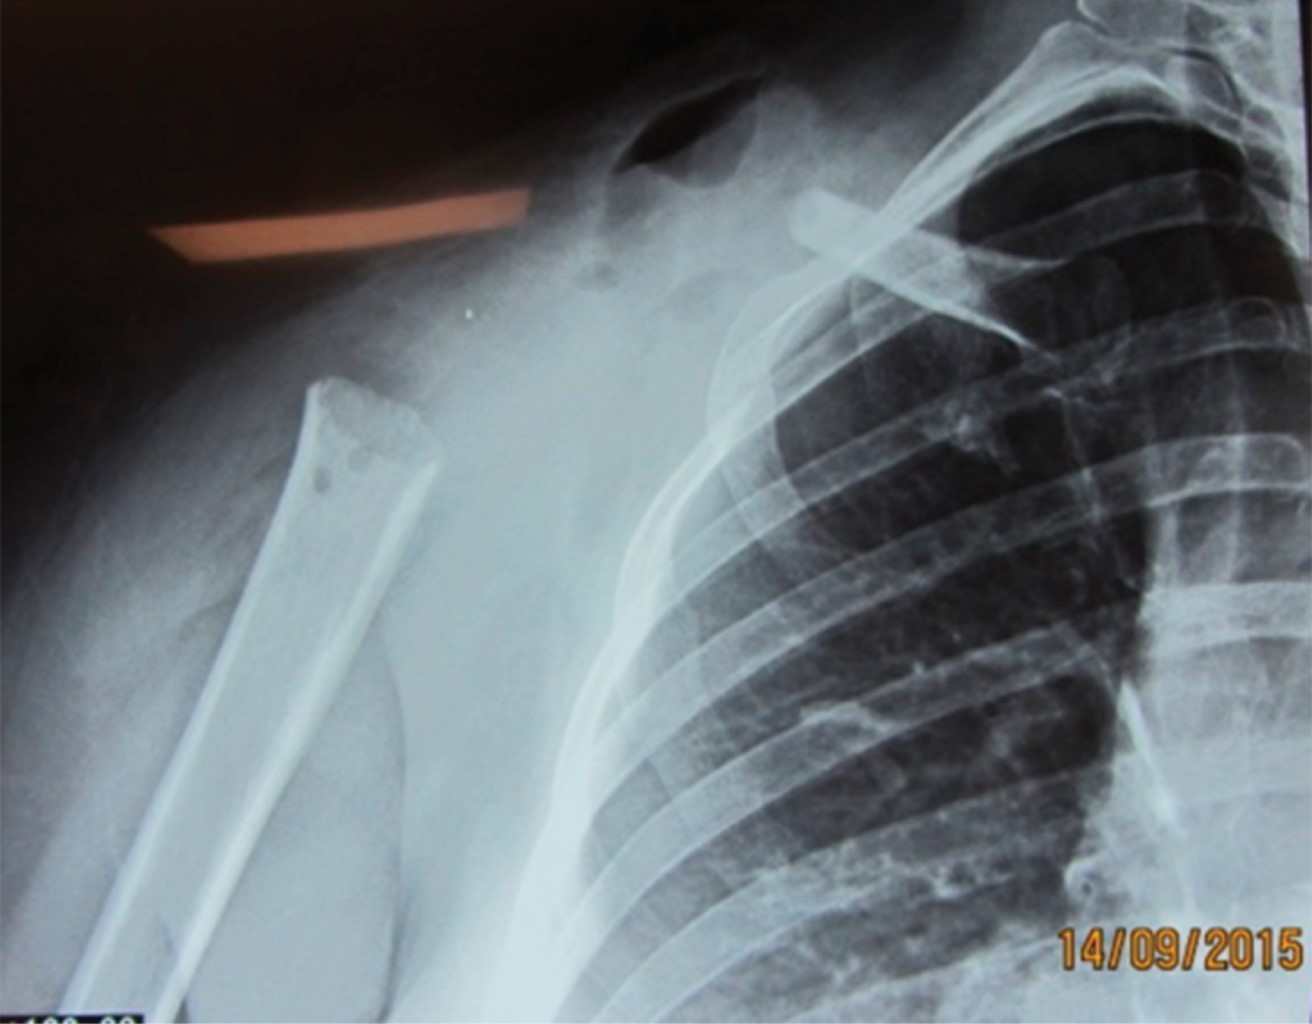

The approximate incidence of this case is 2-5:1'000,000, so it is a very rare entity. In studies where the use of the Tikhoff-Linberg type 4 technique is reported,10,11 scapula and/or humerus prosthesis are used (Figure 7). In this case, an alternative surgical procedure was performed without the use of a prosthesis. This way, the humerus of the residual clavicle was "anchored" using polyester suture (Figure 3), a technique which, despite being described by Linberg,8,11 has not been used in any of the published cases of its use. We show the image of post-procedure radiography (Figure 8).